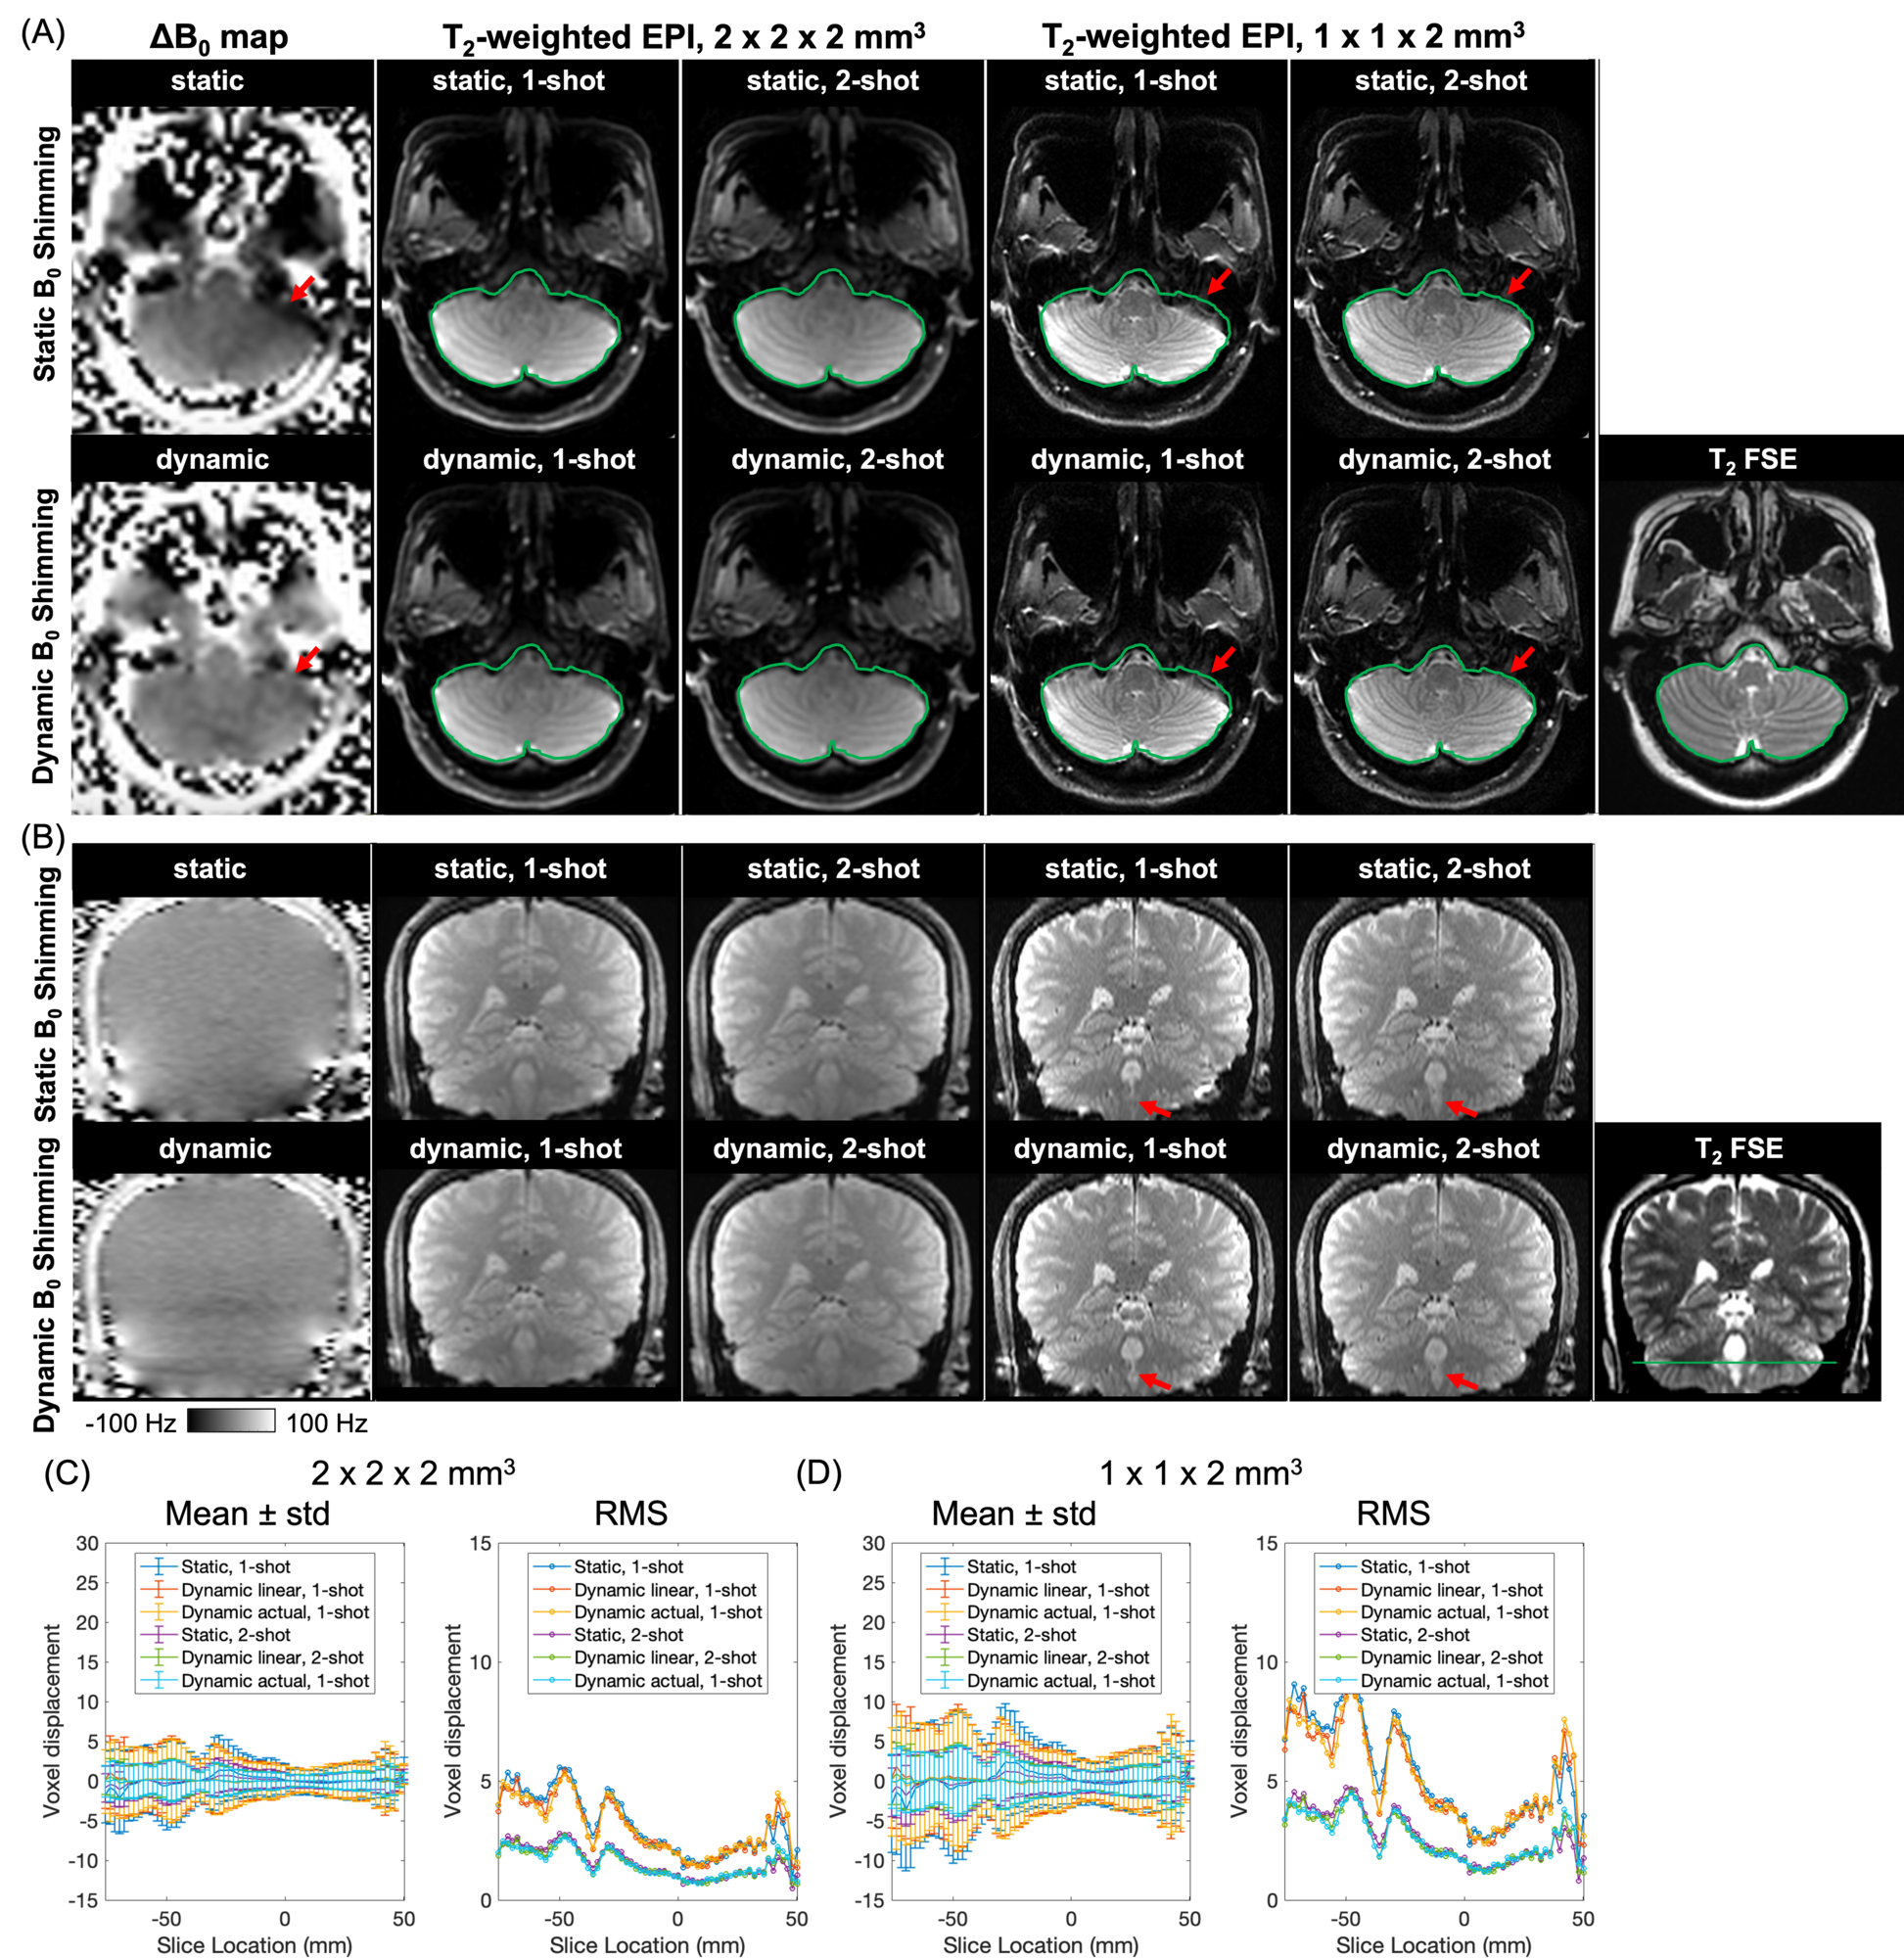

Figure 4 shows the maps, -weighted EPI at 2 x 2 x 2 and 1 x 1 x 2 resolutions, and FSE of representative slices of the mini-ACR phantom in axial (Figure 4A) and sagittal (Figure 4B) views, as well as the mean, standard deviation, and root-mean-square of voxel displacement of each axial slice in single-shot and two-shot EPI acquisitions (Figures 4C and D). By acquiring single-shot EPI with static shimming, image shift and distortion were observed, as indicated in regions highlighted by red circles and rectangles (Figure 4A). For example, the maximum voxel displacement of the hollow rectangle compared to FSE, as indicated by the blue lines in Figure 4A, was 4.26 mm in 2 x 2 x 2 and 7.01 mm in 1 x 1 x 2 images. Both dynamic shimming and two-shot EPI effectively reduce image distortion. The voxel displacement of the hollow rectangle was reduced to 1.62 mm in 2 x 2 x 2 and 2.92 in 1 x 1 x 2 in two-shot EPI with dynamic shimming. Furthermore, by applying dynamic slice-by-slice shimming, both image shift and distortions were further reduced for each slice, as demonstrated in the sagittal reformat (Figure 4B). The mean and root-mean-square of voxel displacement of each slice in single-shot EPI acquisition with dynamic shimming were reduced by a maximum of 10 voxels in 2 x 2 x 2 image (Figure 4C) and 20 voxels in 1 x 1 x 2 image (Figure 4D), compared to single-shot EPI acquisition with static shimming. Two-shot EPI acquisitions with dynamic shimming also achieved reduced mean and root-mean-square of voxel displacement of each slice by a maximum of 5 and 10 voxels in the two resolution images, compared to two-shot EPI acquisitions with static shimming.

Figure 5 shows the maps, -weighted EPI at 2 x 2 x 2 and 1 x 1 x 2 resolutions, and FSE of representative slices of a healthy volunteer’s brain in axial (Figure 5A) and coronal (Figure 5B) views, as well as the mean, standard deviation, and root-mean-square of voxel displacement of each axial slice in single-shot and two-shot EPI acquisitions (Figures 5C and D). Image distortions were more apparent in images with 1 x 1 x 2 resolution, due to the longer echo spacing. Applying dynamic slice-by-slice shimming more apparently reduced distortions of images with 1 x 1 x 2 resolution, especially in slices at the bottom of the brain, as indicated by the green contours and red arrows. Supplementary Figures S2 and S3 showed the voxel displacement of each axial slice in the other two healthy volunteers. In all three volunteers, dynamic slice-by-slice field shimming more efficiently reduced root-mean-square of voxel displacement at the edge of the inferior brain regions. In one subject (Supplementary Figure S2), dynamic slice-by-slice shimming also reduced voxel displacement by a maximum of 3 voxels at 2 x 2 x 2 resolution and a maximum of 6 voxels at 1 x 1 x 2 resolution from slices at -40 mm to 40 ms.